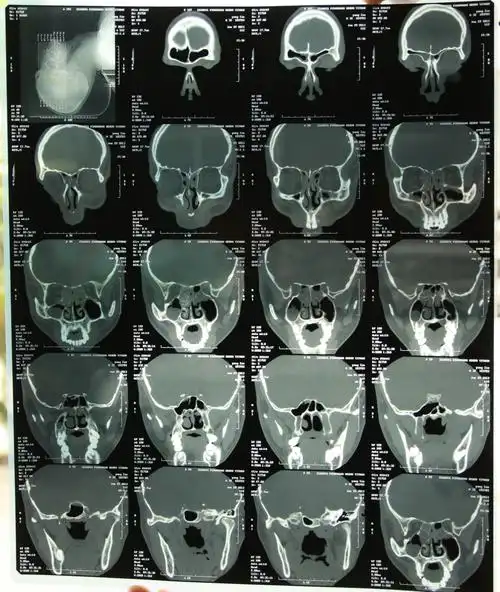

谁来帮忙看下我这张鼻部ct片